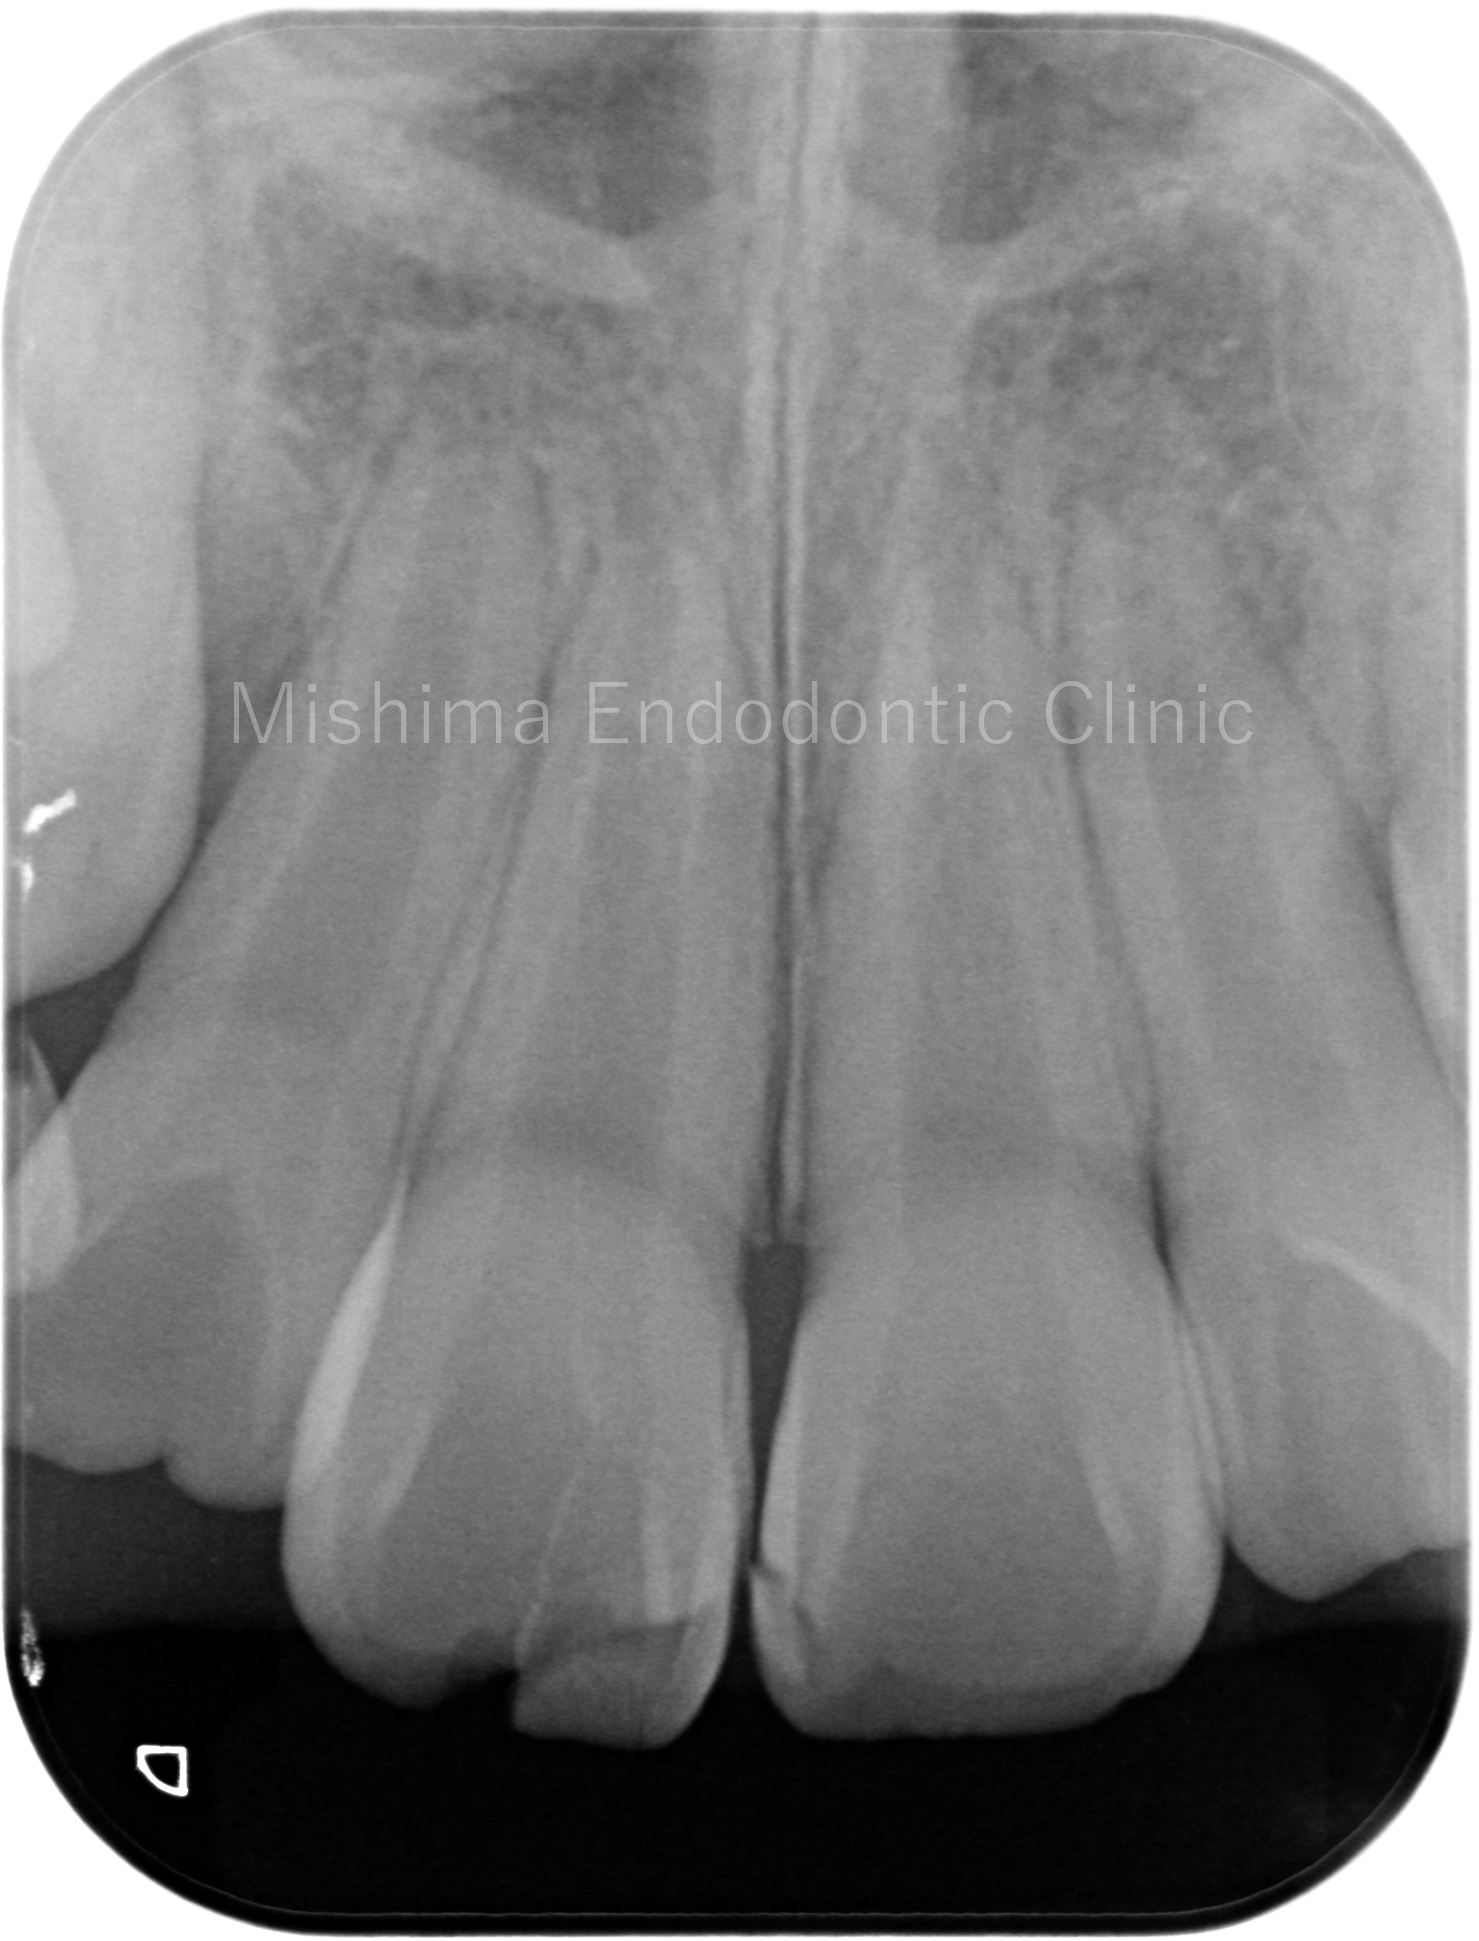

術前

レントゲン